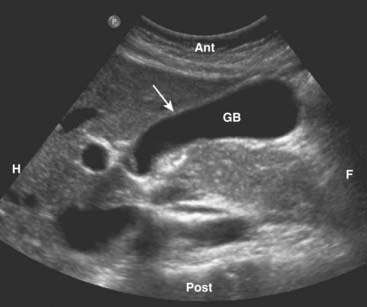

image The gallbladder is an elliptical sac that lies inferior and medial to the right lobe of the liver. Although different layers of its wall have different echogenic properties, the gallbladder overall consists of a fluid-filled sonolucent lumen surrounded by an echogenic wall. In the fasting patient, the gallbladder is about 4 × 10 cm in size and the wall is normally no thicker than 3 mm (Fig. 19-1).

image

Figure 19-1 Normal gallbladder, sagittal view.

The gallbladder (GB) is normally filled with bile and is sonolucent. The wall of the gallbladder is less than 3 mm in size and slightly echogenic (solid white arrow). By convention on a sagittal view, the patient’s head is to your left (H), feet to your right (F), anterior is up (Ant), and posterior is down (Post).